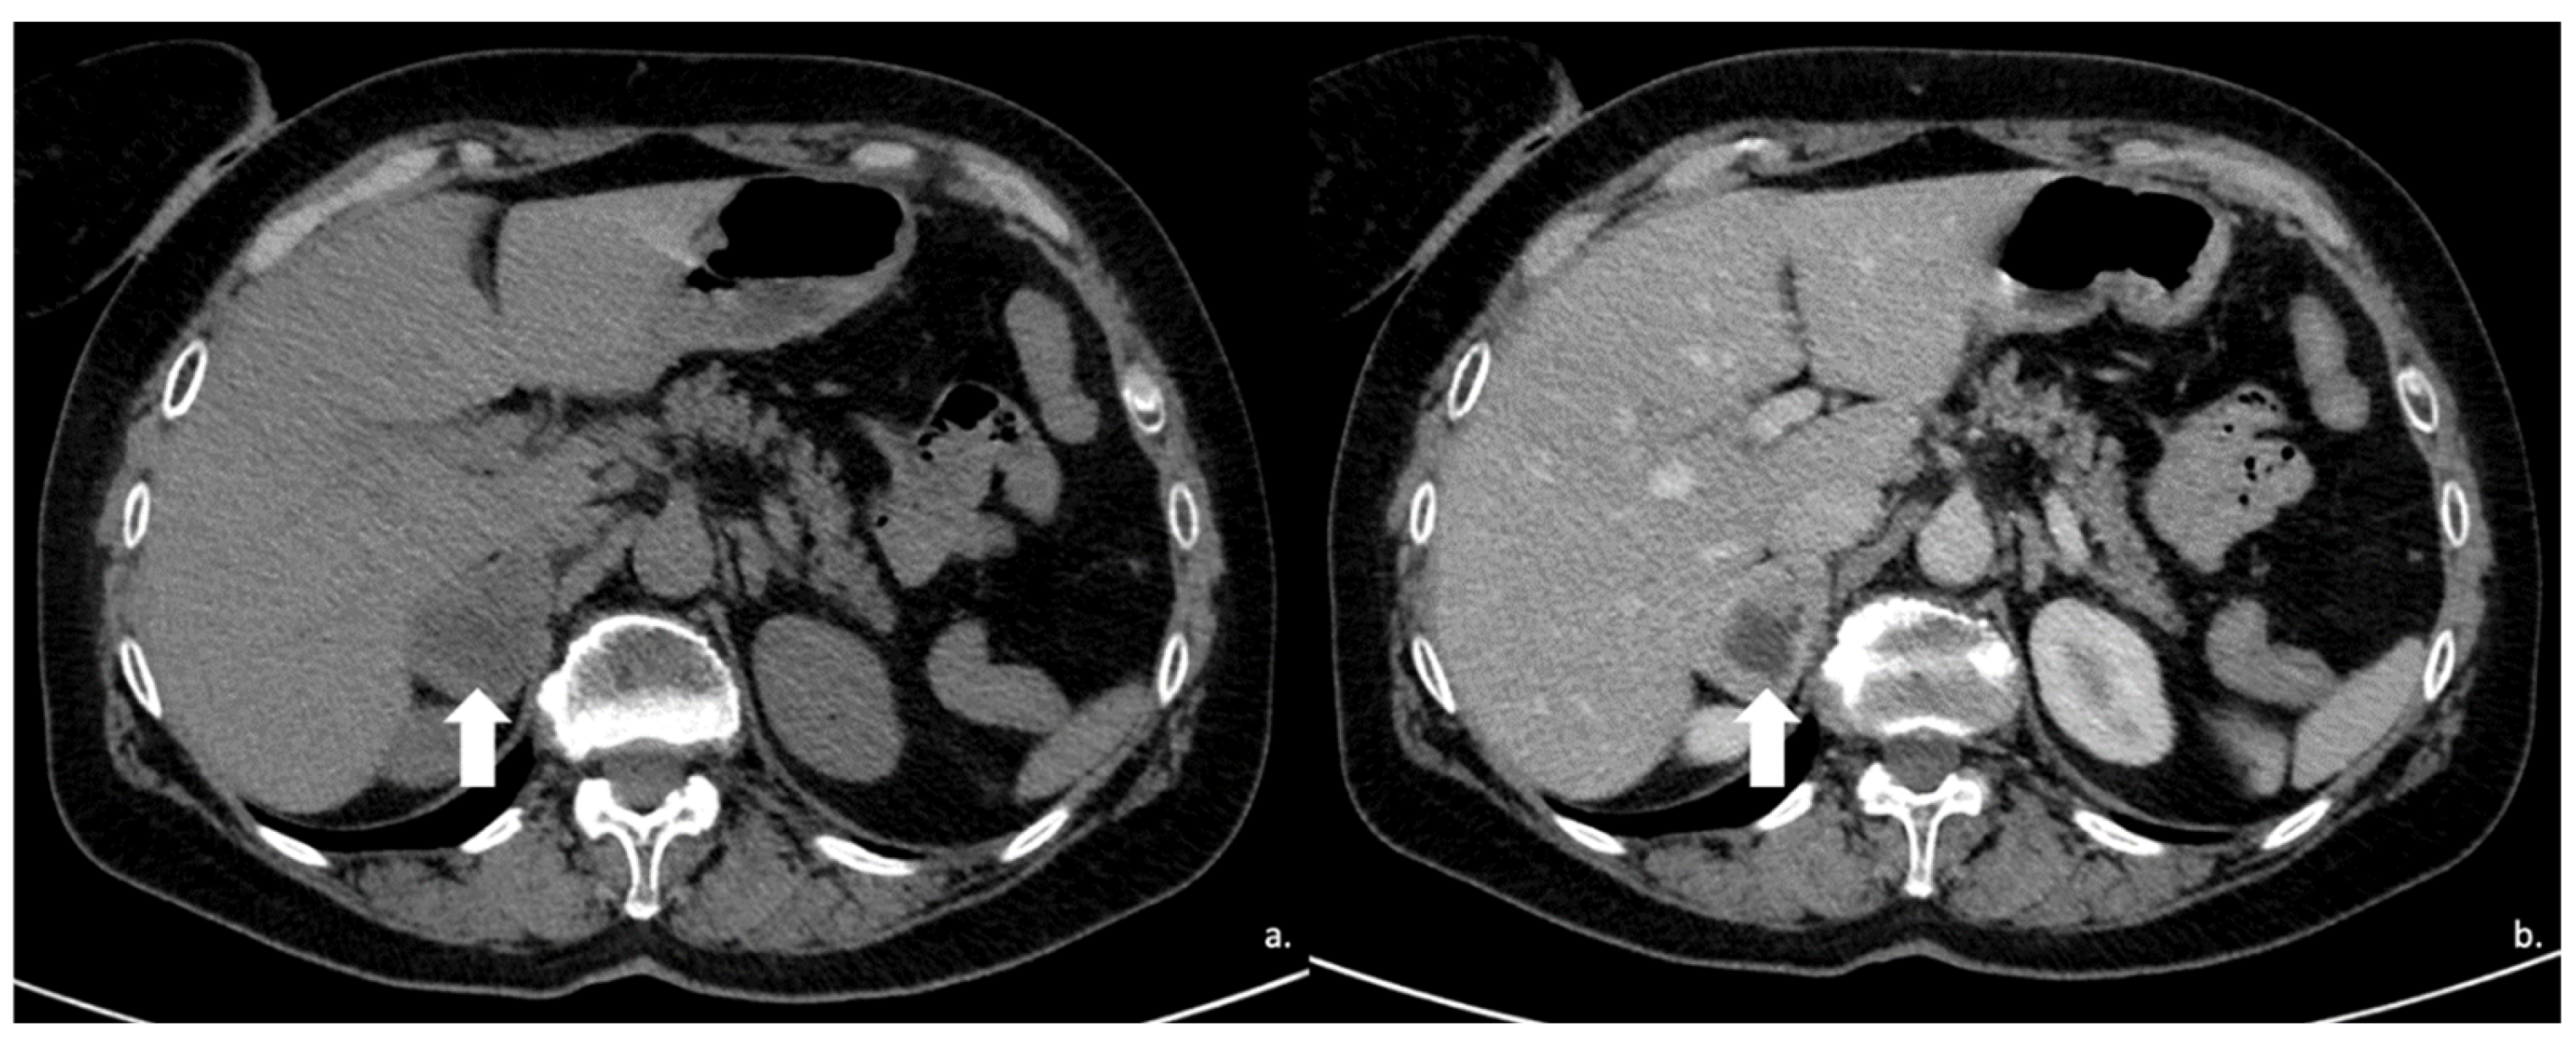

Figure 12.

(a) Unenhanced and (b) venous CT phases show a solid lesion (arrow) in the right adrenal gland with a heterogeneous contrast-enhancement due to necrotic-colliquative phenomena; on histological examination, the lesion was a pheochromocytoma.

Figure 13.

An example of segmentation of an LPA in the right adrenal gland (arrow) in an unenhanced CT phase using 3D Slicer software (version 4.11). The volume of interest (VOI) of the LPA was manually drawn covering the whole lesion.

Figure 16.

(a) Axial and (b) coronal venous phases CT show an ACC of the left adrenal gland presenting as a large mass (arrow) of heterogeneous appearance with extensive neoplastic thrombosis of the ipsilateral renal vein.